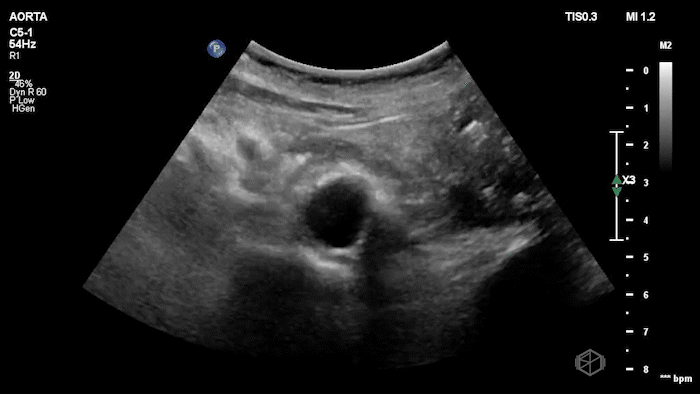

Dr. Flouskakos is on the US rotation currently and was scanning a late 80’s female with mild left lower quadrant and left flank pain when he noticed the following findings:

Upon scanning the aorta, it was noted that the patient an enlarged infra-renal abdominal aorta with an eccentric left thrombus, measuring approximately 4.05cm consistent with an abdominal aortic aneurysm. On lateral view the aneurysm appears more saccular than fusiform. CT was done which confirmed the finding: Saccular infrarenal abdominal aortic aneurysm with partially thrombosed aneurysm sac eccentric to the left measuring up to 4.0 cm.

Diagnosis: Saccular aortic aneurysm